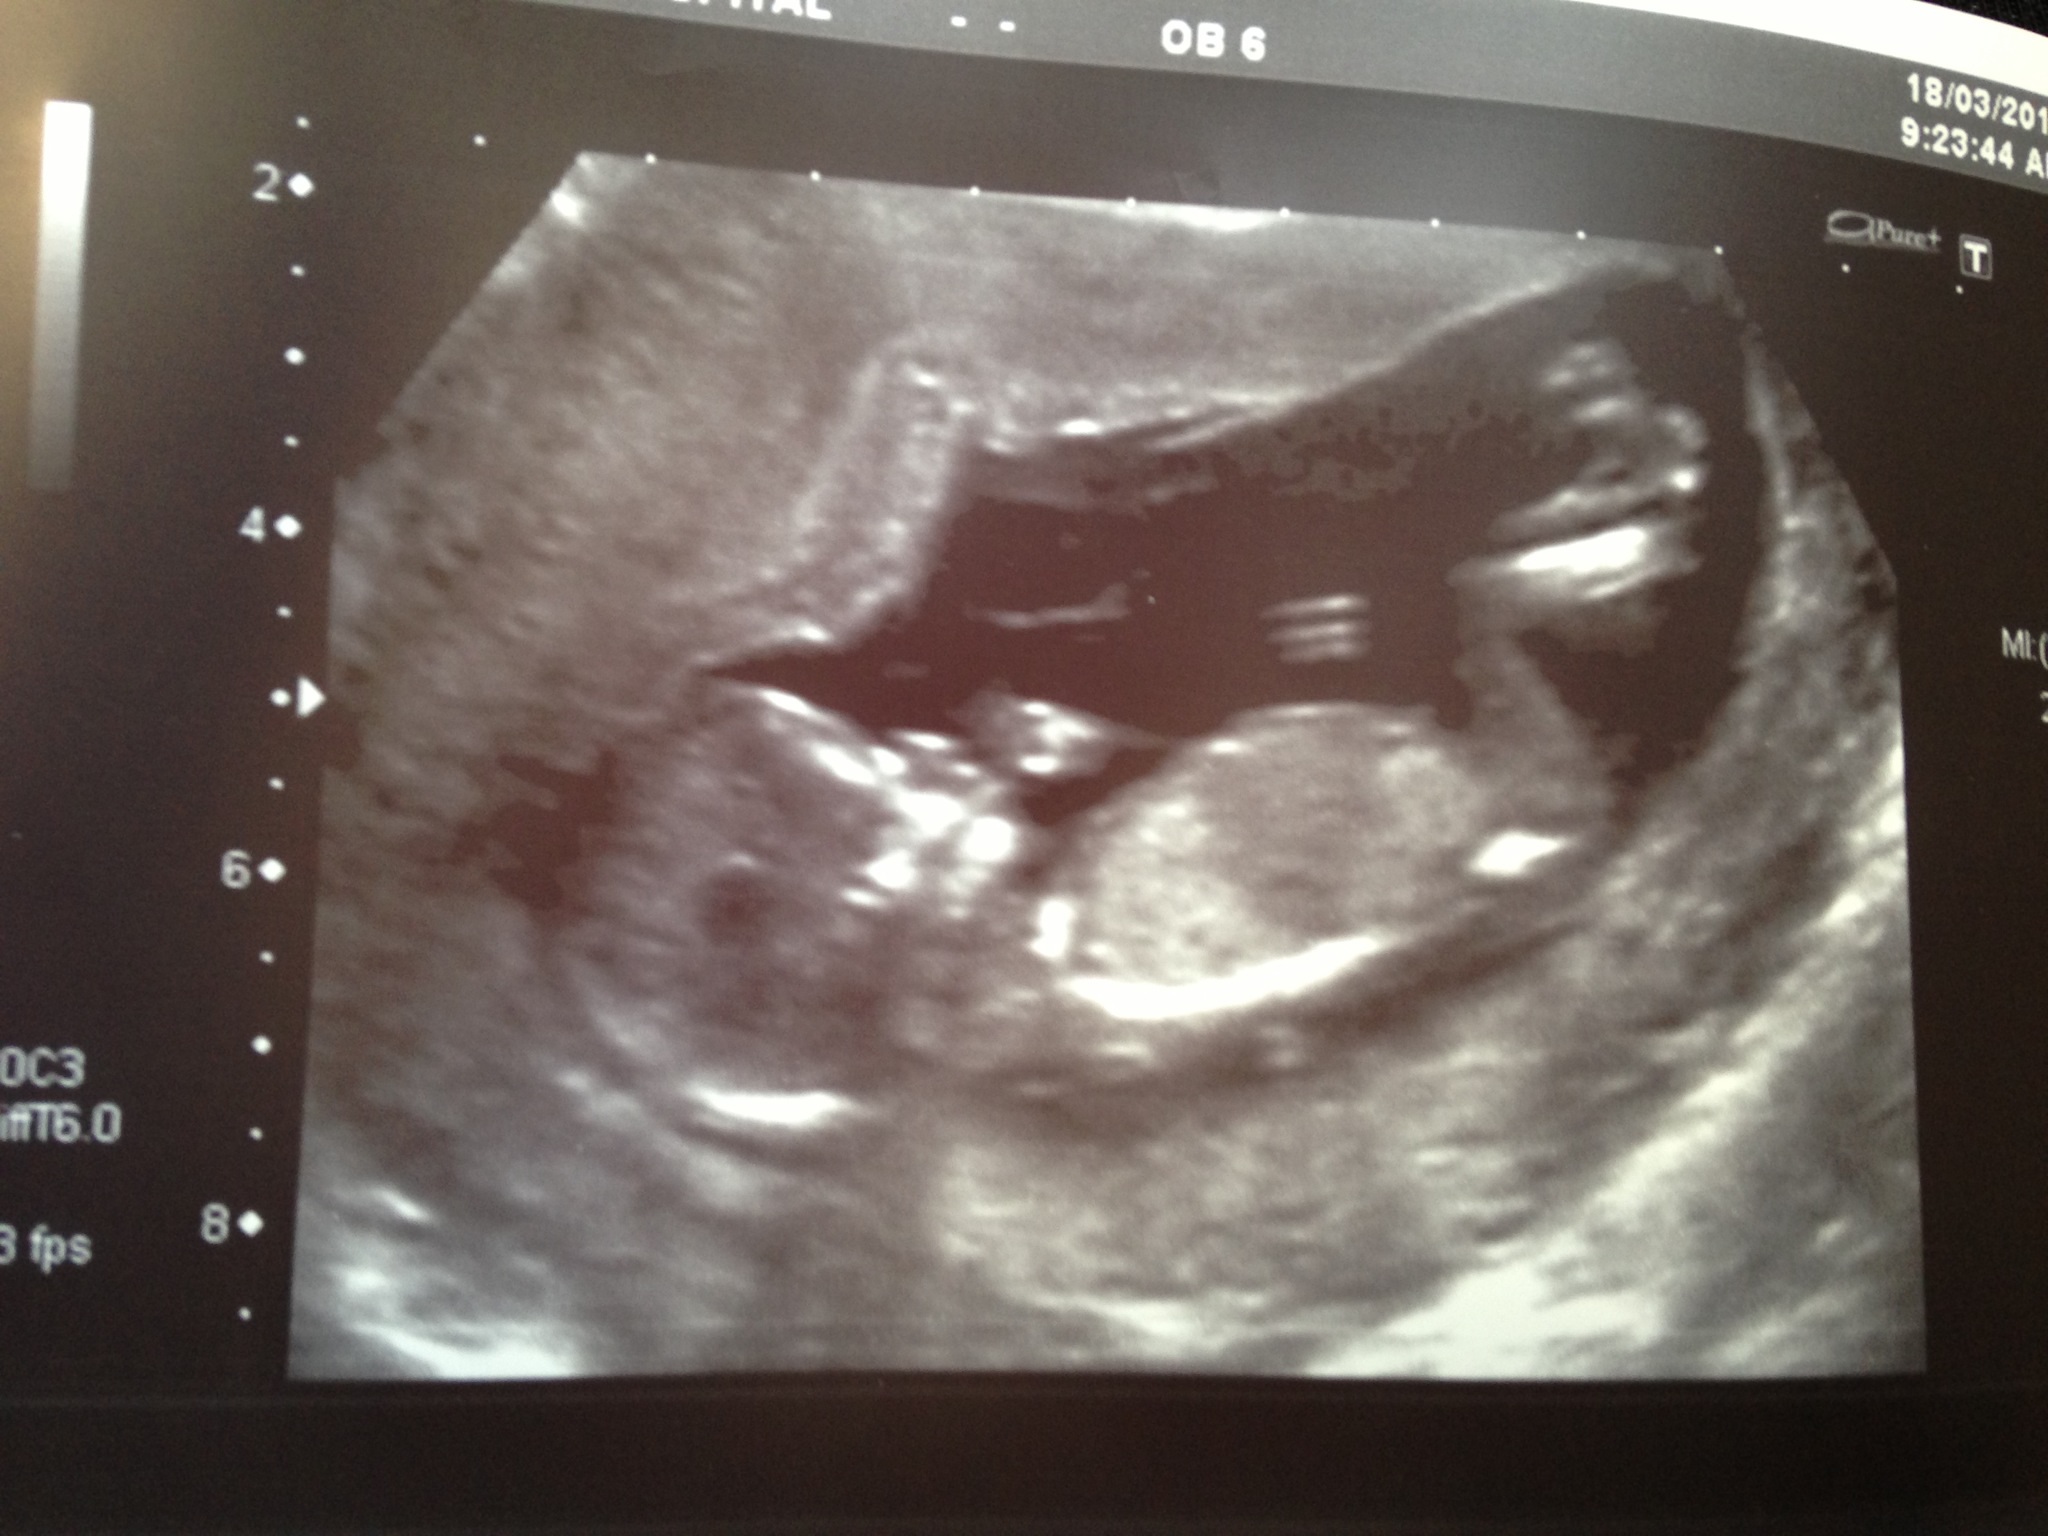

Awwww....I have no idea about how to pick the gender but what a cute pic!! ❤️❤️ Sent from my iPhone using Tapatalk

Girl xx